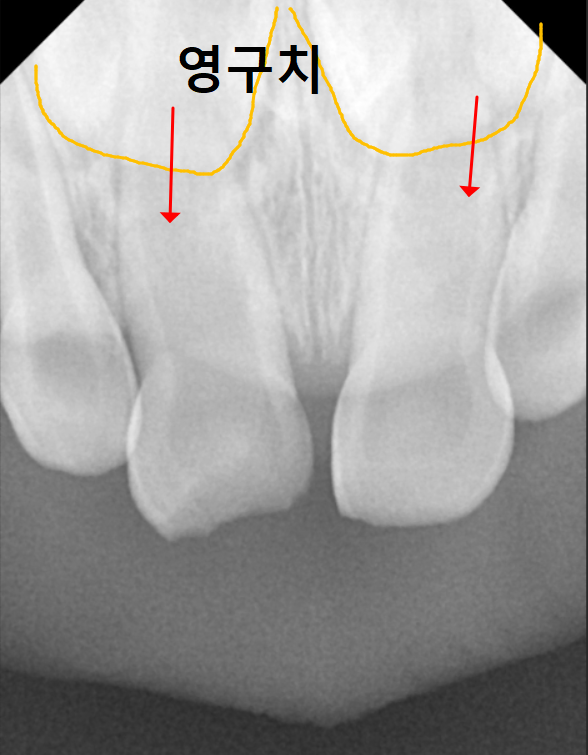

우선 가장 큰 차이는 뿌리의 길이에 있습니다.

유치는 영구치보다 뿌리가 훨씬 짧다 보니

성인의 강한 씹는 힘을 수십 년간

온전히 견뎌내기에는

아무래도 무리가 따를 수밖에 없답니다.

엑스레이를 찍어보니

아주 짧고 가느다란 유치 뿌리가 보입니다.

일반적인 송곳니들은

다른 치아들에 비해 뿌리가 긴 편인데,

유치는 영구치에 비해

상대적으로 뿌리가 짧다보니,

사용할 수 있는 기간이 더 짧을 수 밖에 없어요.